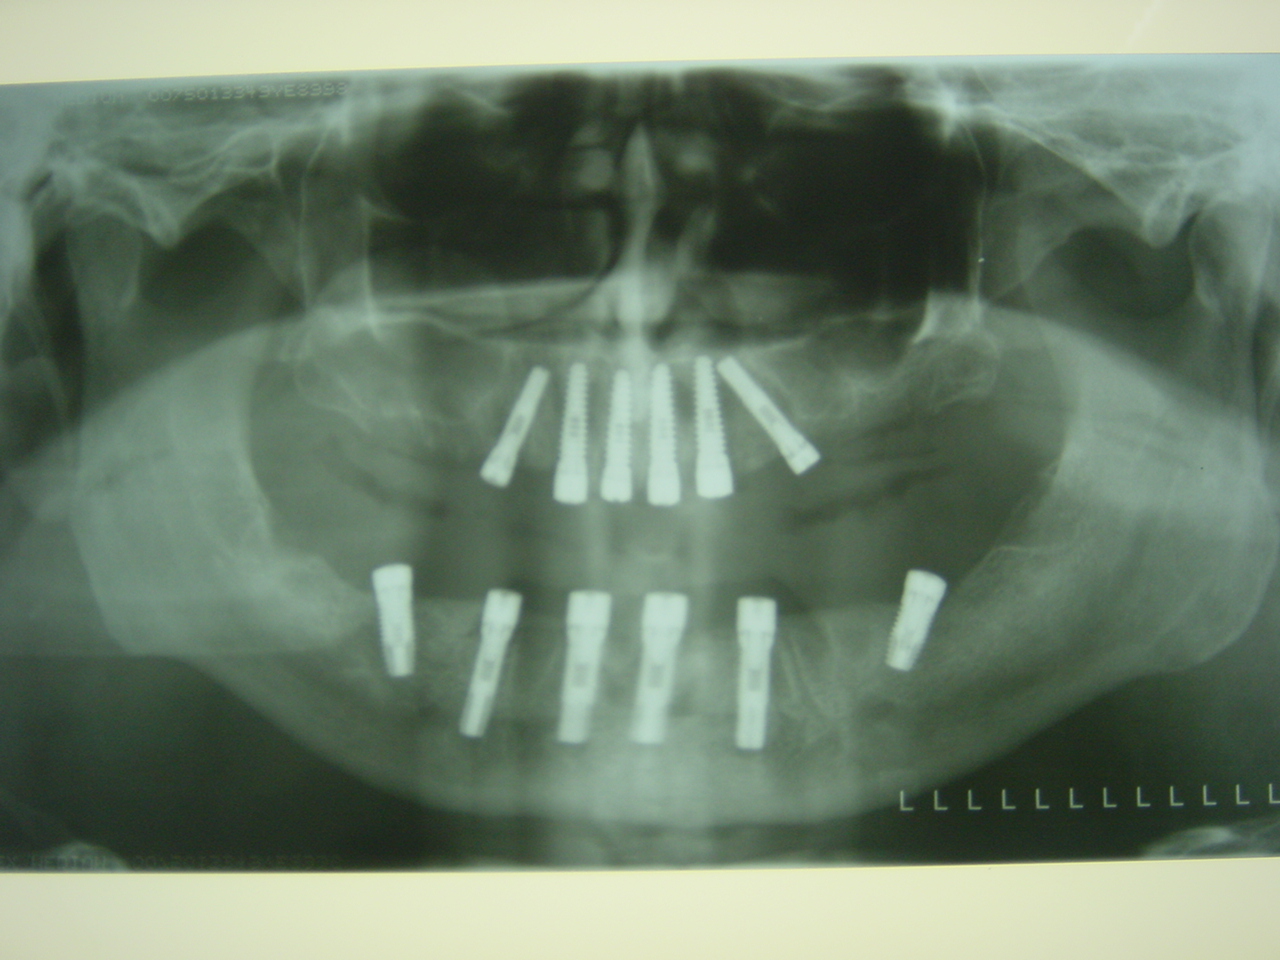

6-implants-in